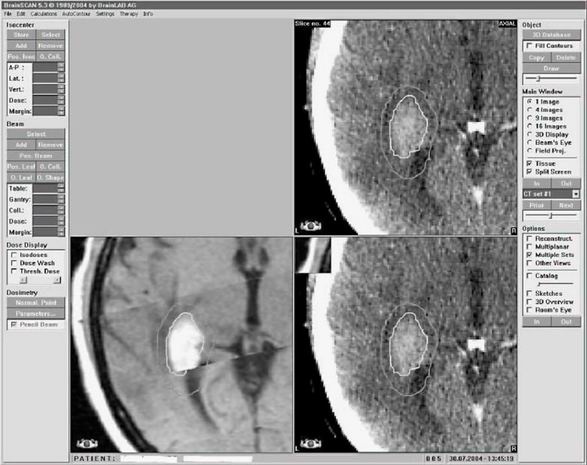

Ke snížení procenta komplikací je dnes nutné využít 3D plánování pomocí CT vyšetření a označení všech kritických orgánů

– jater, kontralaterální ledviny, míchy apod. Velmi důležitá je definice cílového objemu, vhodné je využití chirurgických klipů označujících lůžko ledviny. Samozřejmostí je rovněž výpočet objemové dávky jednotlivých orgánů (histogram dávka/objem). Tím významně eliminujeme procento komplikací radioterapie, kterým byly zatíženy historické studie. Stein a spol. uvádí snížení komplikací u skupiny 56 pacientů léčených pooperační radioterapií v dávce 46 Gy na 5 % (pouze u 3 pacientů z celkového počtu 56 nemocných).